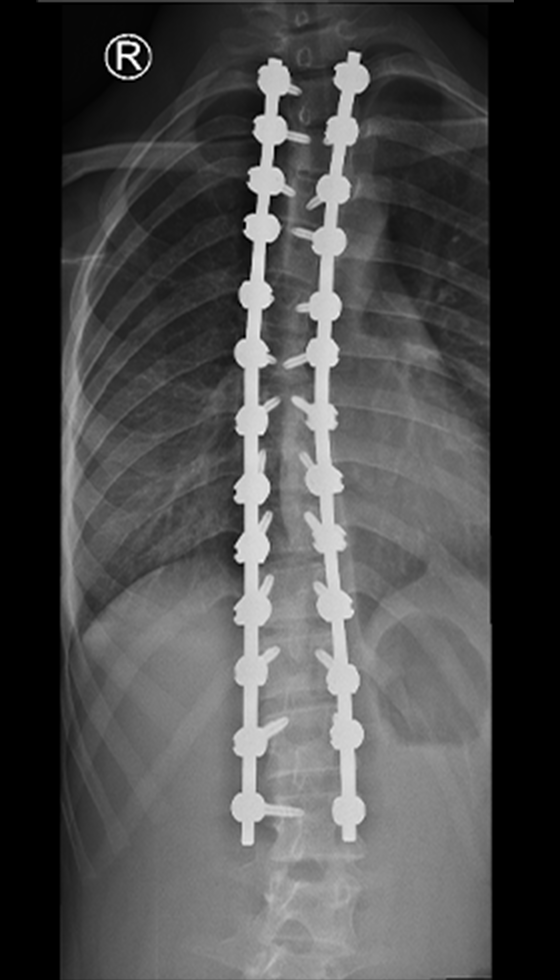

Gallery : Before - After